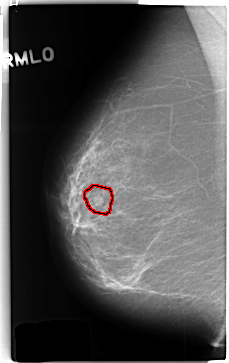

C_0370_1.RIGHT_MLO

RIGHT_MLO LINES 4712 PIXELS_PER_LINE 2968 BITS_PER_PIXEL 12 RESOLUTION 50 OVERLAY

FILE: C_0370_1.RIGHT_MLO.OVERLAY

TOTAL_ABNORMALITIES 1

ABNORMALITY 1

LESION_TYPE MASS SHAPE LOBULATED MARGINS CIRCUMSCRIBED

ASSESSMENT 3

SUBTLETY 4

PATHOLOGY BENIGN

TOTAL_OUTLINES 1